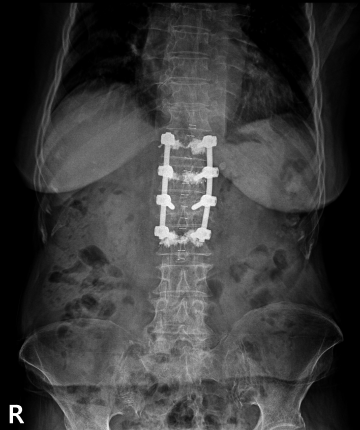

수술

치료

척추 고정술 치료 방법

2020.06.09

2020.08.11

ㆍ환자 동의를 받은 자료이며, 이미지 사진은 실물과 다를 수 있습니다.

ㆍ모든 자료는 새움병원 자료입니다.